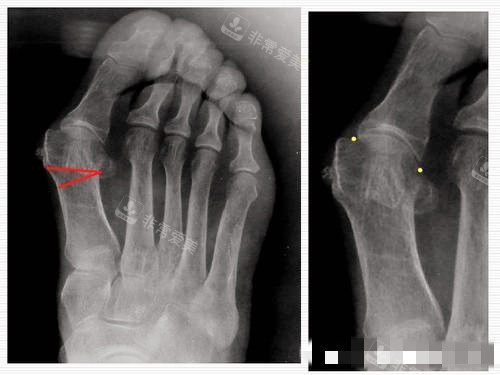

大脚骨X光片图片